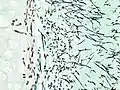

| Tomosynthesis of chronic fibrosing pulmonary aspergillosis | |

On microscopy, Aspergillus species are reliably demonstrated by silver stains, e.g., Gridley stain or Gomori methenamine-silver.[27] These give the fungal walls a gray-black colour. The hyphae of Aspergillus species range in diameter from 2.5 to 4.5 μm. They have septate hyphae,[28] but these are not always apparent, and in such cases they may be mistaken for Zygomycota.[27] Aspergillus hyphae tend to have dichotomous branching that is progressive and primarily at acute angles of around 45°.[27]

Pulmonary invasive aspergillosis in a person with interstitial pneumonia (autopsy material), using Grocott's methenamine silver stain